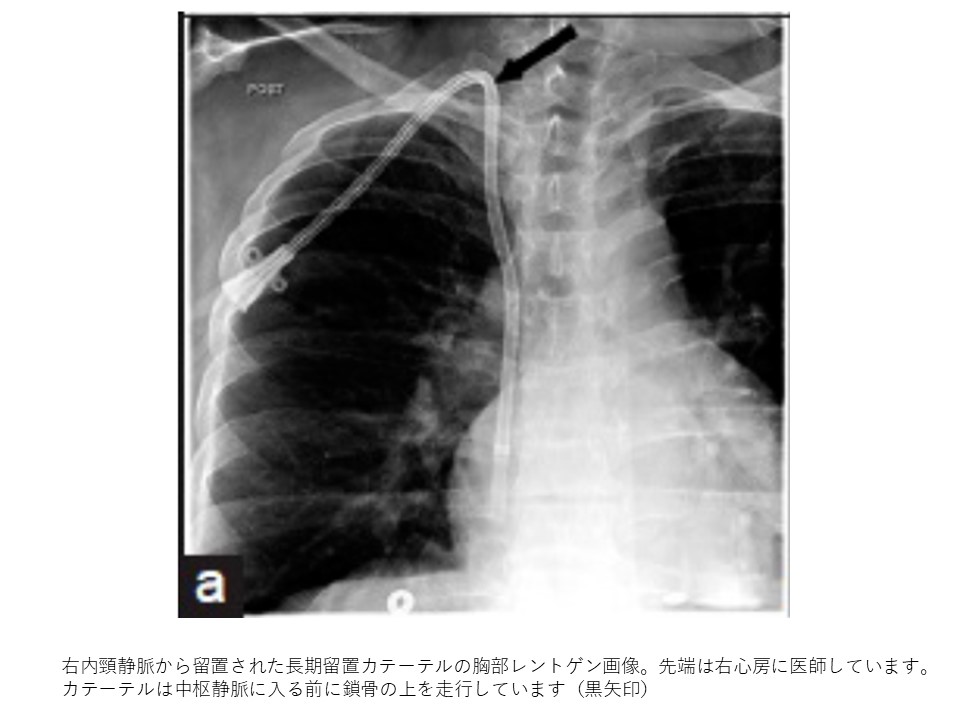

画像引用:Subclavian or Internal Jugular Tunneled Dialysis Catheter: Can we Divulge the Location?

先端位置と長さー右房内の判断

長期留置カテーテルの先端位置は右房内がいいですが、カテーテル本体が長すぎると右房壁に接触してしまう危険性があるので、長すぎる場合は、カテーテル先端を下大静脈内に留置することがあります。